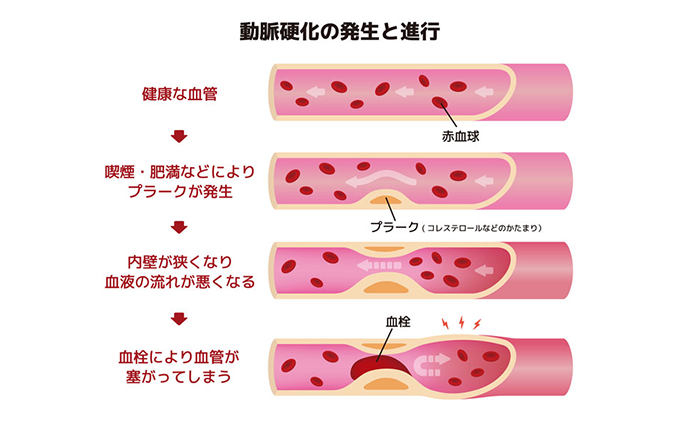

高脂血症とは、血液中の脂質(血清脂質)が異常に高い状態を指します。

自覚症状はありませんが、血管内に蓄積した脂質は、直接動脈硬化を引き起こします。それでも症状は現れずに進行し、重大な問題、つまり心筋梗塞や脳血管障害を引き起こしてしまいます。

歯周病(歯槽膿漏)の人はそうでない人に比べて、心筋梗塞などの心臓血管疾患にかかる確率が高くなるという驚くべき研究結果が米国で報告され、最近大きな話題となっています。

心臓血管疾患で、最近、重視されているのは脳梗塞、心臓冠動脈疾患、心臓発作、末梢動脈疾患などの原因となる粥腫血栓症(アテローム血栓症)です。

この粥腫血栓症(アテローム血栓症)は酸素や栄養を運ぶ太い動脈の中で血栓を作って症状を引き起こします。欧米に多く、日本には少ないと言われていましたが、生活習慣や食生活の変化とともに日本でも増加傾向にあります。

この血栓を作る危険因子は、機械的ストレス、喫煙、高コレステロール血症そして歯周病(歯槽膿漏)のような直接的・間接的な細菌感染です。

歯周病(歯槽膿漏)の炎症を起こす細菌の毒素は、歯肉から血液に入ってしまう事でこの血栓を作りやすくします。

重度の歯周病(歯槽膿漏)患者とそうでない人を比べると、冠動脈疾患を引き起こす可能性が2倍程高いと言われていますので、しっかりと治療を行うことが重要です。